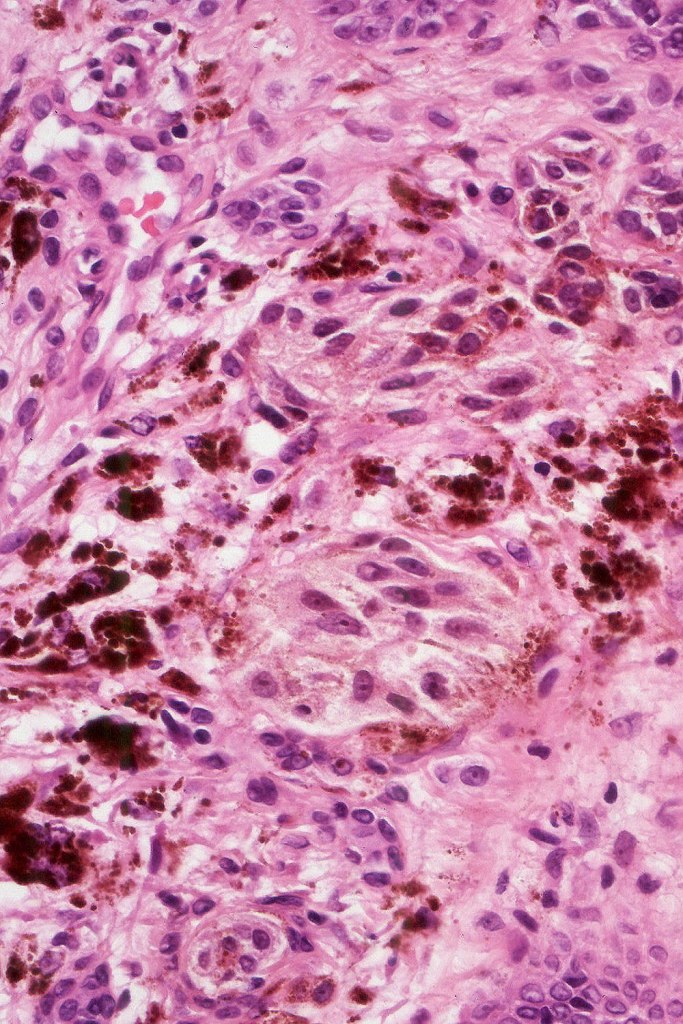

Combined common melanocytic nevus & BAP1-inactivated melanocytoma